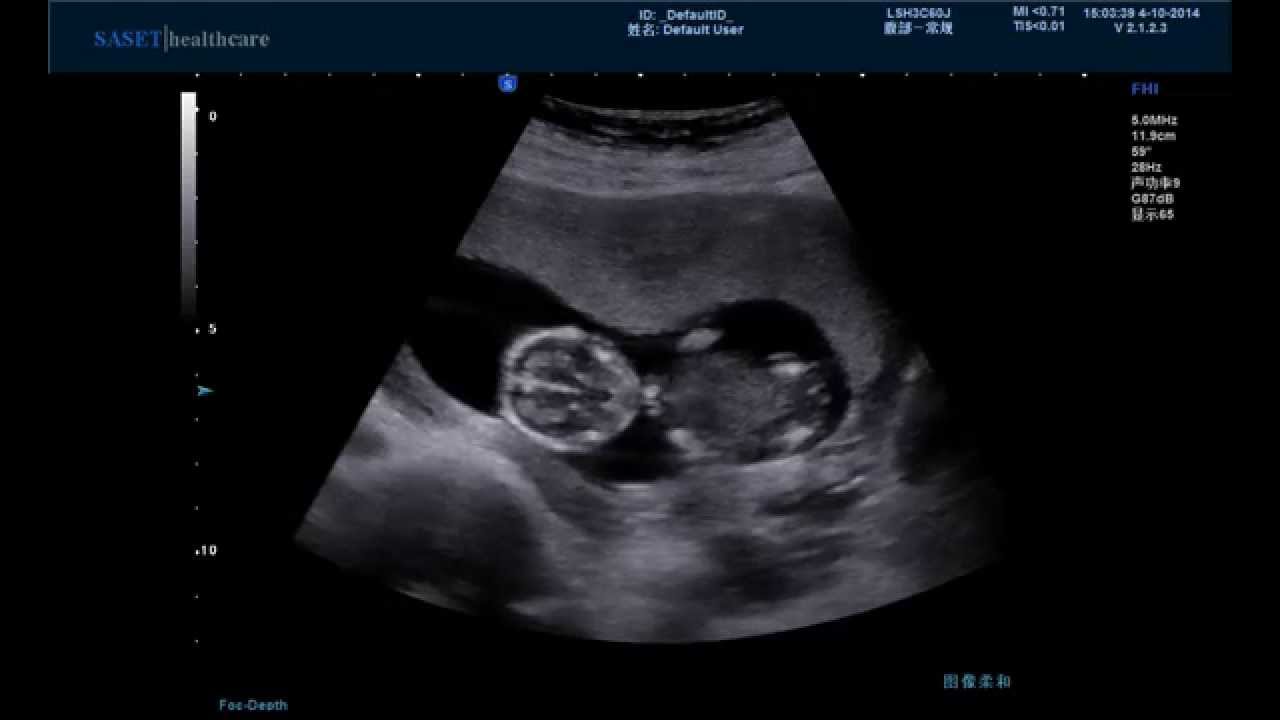

| هل السونار يضر الجنين !! |

| 03-04-2016 11:07 AM |

قد تشعر المرأة أحيانًا ببعض القلق حول الخضوع لفحص بالموجات فوق الصوتية أو ما يعرف أيضًا بالسونار بسبب كثرة الأقاويل حول احتمال تأثير الذبذبات على نمو الجنين. فهل تعتبر هذه... |